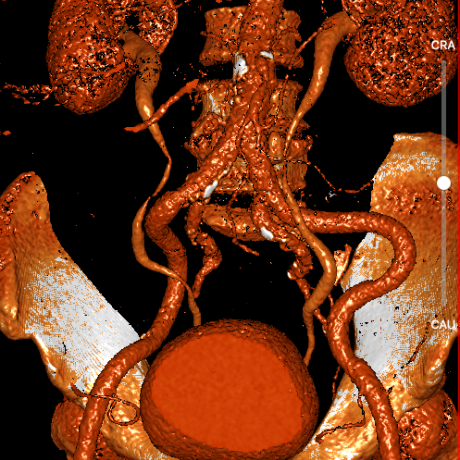

武汉协和董念国团队对该病例进行了缜密探讨,该病例为老年男性,主动脉瓣中重度狭窄,术前左室舒张功能减低。患者病例CT和心超数据显示瓣环周长:90.2mm,瓣下4mm流出道周长:97.5mm,窦部空间相对小,单纯无冠瓣瓣叶钙化,三叶瓣。左冠风险较高,缜密分析瓣叶遮盖率>50%,术中可能存在阻挡风险,需要术中球囊扩张时仔细辨认,并准备冠脉保护策略。综合评估考虑右股动脉更适宜为主入路。经过团队严谨的评估及充分的讨论,决定先行25mm球囊预扩并进一步确认冠脉风险,并准备TAV29和TAV32规格的ProStyle预装式可回收TAVR系统。

腹主-股动脉入路

主动脉弓降入路